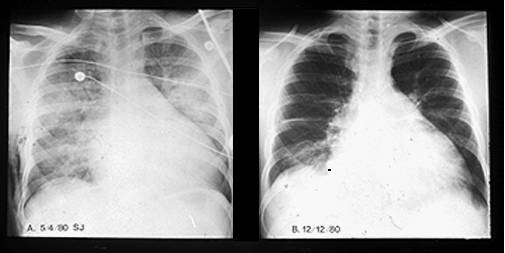

Evolutia este variabila - la jumatate din bolnave modificarile morfologice, dilatatia cardiaca si fenomenele de insuficienta cardiaca dispar in 6-12 luni. La jumatate evolutia este continua si rapida spre exitus sau lenta spre insuficienta cardiaca cronica.

Tratamentul este asemanator CMD idiopatice. Mijloacele de tratament trebuie folosite maximal. Se interzice alaptarea la san in formele relativ severe de insuficienta cardiaca. Persistenta disfunctiei cardiace peste 6 luni necesita masuri anticonceptionale.